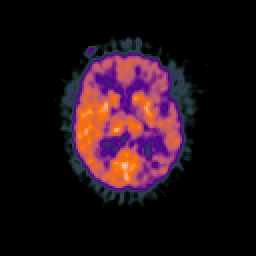

Glioma overlay -- Slice #61

[Home][Help][Clinical] Slice 61